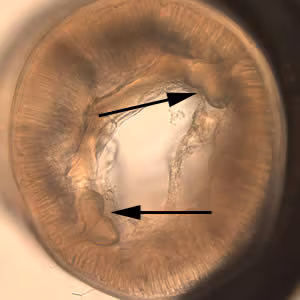

A 4-year-old boy’s parents discovered a worm that they thought had been spit out by their child. They submitted the worm to their physician, along with the information that the boy had some exposure to raw seafood and that the family had a dog. The worm was eventually sent to a state public health laboratory and then CDC for identification. The worm was approximately 2 cm in length (see Figure A). The worm was cleared with lacto-phenol but defining morphologic features could not be seen. The posterior end was difficult to examine due to the cuticle being “rolled up” (see Figure B, 40× magnification). The anterior end was broken off (see Figure C, 40× magnification). A small cross-sectional slice of the worm was obtained with a scalpel and placed on a microscope slide with the cut side facing up. A small amount of lacto-phenol was placed around the section and a coverslip “floated” gently onto it, with additional solution along the edges of the coverslip to make an effective seal. Figure D, taken at 100× magnification shows what was observed in the section. What is your diagnosis? Based on what criteria?

Figure D